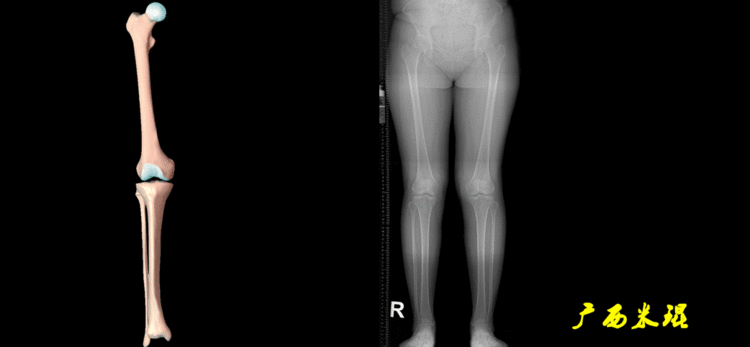

4、画出与机械轴相关的角度股骨近端外侧角(LPFA):沿股骨头中心与大粗隆最高点划一直线,连接股骨头中心与膝关节中心划一直线(机械轴),两者之间形成的外侧夹角,正常为90°±5°。

股骨远端外侧角(mLDFA):股骨内外侧髁远端切线(关节线)与股骨头和膝关节中心的连线(机械轴)两者之间形成的外侧夹角,正常为87°±3°。

胫骨近端内侧角(mMPTA):胫骨内外侧平台切线(关节线)与股骨头和膝关节中心的连线(机械轴)两者之间形成的内侧夹角,正常为87°±3°。

胫骨远端外侧角(mLDTA):胫骨远端切线(关节线)与下肢力线(机械轴)两者之间的外侧夹角,正常为89°±3°。

5、画出与解剖轴相关的角度解剖股胫角(aFTA):股骨干下段轴线(解剖轴)与胫骨上段轴线(解剖轴)在膝关节所形成的夹角,正常为174°±1°。膝关节OA的畸形常常由于一侧软组织及关节的过度磨损所致,临床多为内侧磨损过度,因此表现为轻度膝内翻畸形,X线表现为解剖股胫角小于174°,而胫骨角正常。

解剖股骨远端外侧角(aLDFA):股骨干下段轴线(解剖轴)与股骨内外侧髁远端切线(关节线)在膝关节外侧所形成的夹角,正常为81°±2°。大多数膝外翻患者的畸形发生于股骨下端,表现为股骨远端外侧角小于正常值。

解剖胫骨近端内侧角(aMPTA):胫骨内外侧平台切线(关节线)与胫骨解剖轴两者之间形成的内侧夹角,正常为87°±3°。由于胫骨解剖轴与机械轴几乎一致,所以一般解剖胫骨近端内侧角与机械胫骨近端内侧角一致。

解剖胫骨远端外侧角(aLDTA):胫骨远端切线(关节线)与胫骨解剖轴两者之间的外侧夹角,正常为89°±3°。由于胫骨解剖轴与机械轴几乎一致,所以一般解剖胫骨远端内侧角与机械胫骨远端内侧角一致。

解剖胫骨近端外侧角(也叫aMPTA):胫骨干上段轴线与胫骨平台切线(关节线)在膝关节外侧所形成的夹角,常称为胫骨角,正常为87°±3°。大多数膝内翻患者的畸形发生于胫骨上端,表现为胫骨角大于90°。严重的膝内翻畸形发生在整个下肢,股骨干及胫骨干都有可能形成向内弯曲的弧形。

6、其他角度胫骨股骨关节线夹角(JLCA):胫骨近端关节线与股骨远端关节线之间的夹角,正常生理状态下几乎为0°。当JLCA>2°时提示异常,通常为韧带松弛或者软度磨损丢失所致。

股骨解剖机械轴角(aMFA):股骨解剖轴与机械轴形成的夹角,正常为6°±1°。

股骨垂直机械轴角(MA):股骨机械轴与身体垂直轴形成的外翻角,正常为3°。